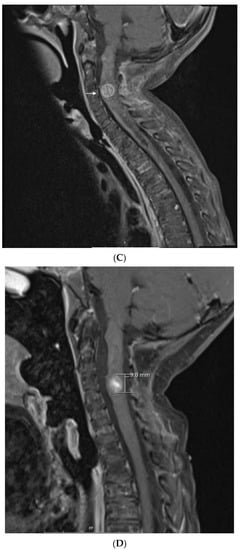

Collectively, these observations have led us to propose a study that incorporates tyrosine kinase inhibitors (TKI) to metronomic chemotherapy. Our backbone of choice to compare with TKI is celecoxib-valproic acid based on our experience and the growing interest in anti-histone drugs that have undergone trials with responses in difficult pediatric tumors [47]. All patients will receive alternating cyclophosphamide and etoposide as described in this report. This study depicted in Figure 5 will involve screening refractory patient’s tumors for metabolic targets, and treating the patients with alternating etoposide-cyclophosphamide and either continuous celecoxib-valproic acid or continuous TKI if a targetable aberrant metabolic pathway is identified.

Figure 5.

Schematic of future planned studies for pediatric cases eligible for metronomic chemotherapy. Proteomic and metabolic pathway analysis, where feasible, will be used to determine eligibility of patients to receive specific tyrosine kinase inhibitor (TKI) therapy coupled with metronomic chemotherapy, which involves alternating cycles of metronomic etoposide with metronomic cyclophosphamide. Patients not selected or not eligible for TKI-based therapies will receive valproic acid (VA) and celecoxib with metronomic chemotherapy as outlined in this manuscript.